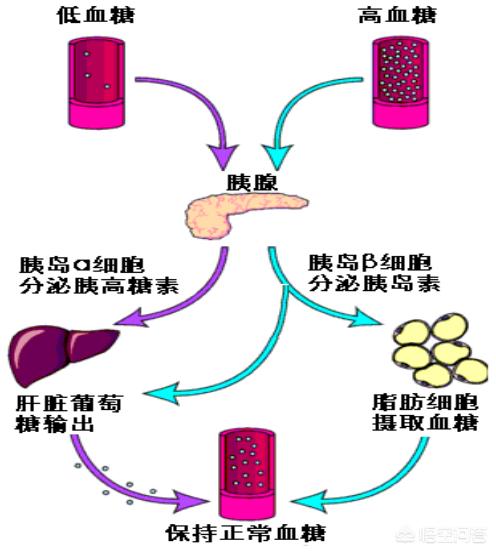

糖尿病とは何かということから始めよう。

糖尿病は、遺伝的、自己免疫的、環境的原因による慢性的な血糖上昇を特徴とする代謝性疾患である。

この病気では、インスリンの分泌や作用の機能障害により、三大栄養素のバランスが崩れ、水電解質や酸塩基のバランスも崩れる。

糖尿病はその原因によって以下のように分類される。

I. 1型糖尿病(B細胞破壊によるインスリン分泌不全)

2型糖尿病(インスリン抵抗性を伴うインスリン分泌不全)

III.その他の特殊な糖尿病

感染症、薬物、化学物質による糖尿病、遺伝子変異による糖尿病、妊娠糖尿病など。